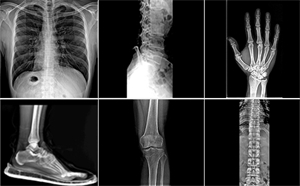

医用高频高压发生器:便携 DR 的 “动力心脏”,决定移动拍片稳定性与成像质量

便携式宠物 DRX 光机:宠物诊所高效拍片的实用选择

河北电力企业探询X光机技术,瞄准检测绝缘子内部缺陷